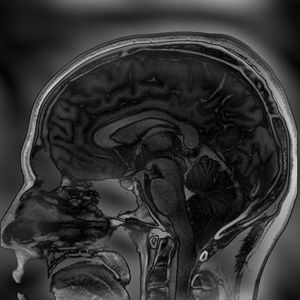

Signal, contrast and resolution information in k-space. If we erase the middle of k-space and just reconstruct the outside data we can see where the tissue boundaries are, but the signal-to-noise ratio (SNR) is low and we have no contrast information. Clearly we need both parts of k-space to get a useful MR image! This image has been reconstructed by the application "2D-Fourier".